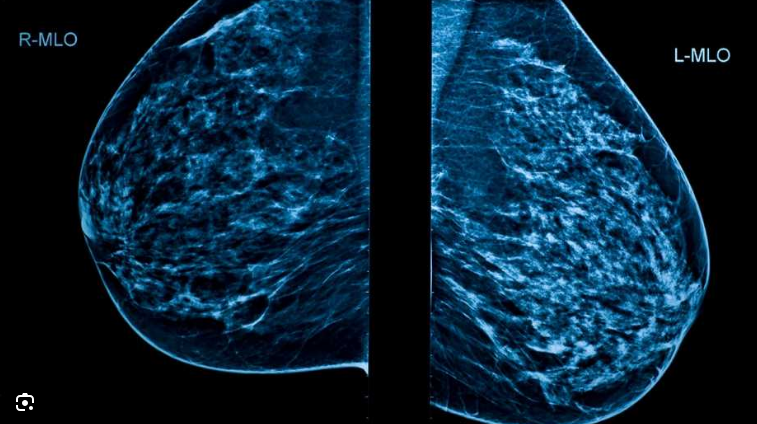

Una mamografía es una radiografía de las mamas. Se puede utilizar para el examen de detección del cáncer mamario o con fines diagnósticos, como para investigar síntomas o hallazgos inusuales en otra prueba por imágenes.

Durante una mamografía, las mamas se comprimen entre dos superficies firmes para estirar el tejido mamario. Entonces, una radiografía captura imágenes en blanco y negro que se muestran en la pantalla de una computadora y se examinan en busca de signos de cáncer.

Una mamografía tradicional crea imágenes bidimensionales de la mama. Un nuevo tipo de mamografía, denominada mamografía 3D (tomosíntesis mamaria), crea imágenes tridimensionales de la mama. Muchos centros médicos ofrecen la mamografía 3D además de la mamografía tradicional 2D para la detección del cáncer mamario.

Las mamografías, también llamadas mamogramas, son imágenes en blanco y negro del tejido mamario. Son imágenes digitales que aparecen en la pantalla de una computadora. Un médico especializado en interpretar pruebas por imágenes (radiólogo) examina las imágenes.